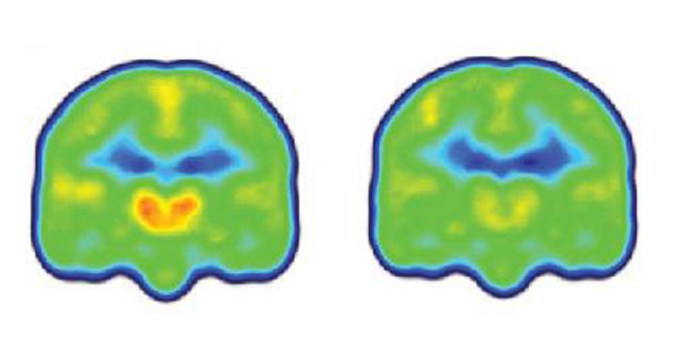

Chronic pain treatments may get boost from high-tech imaging

Advanced imaging may reveal how well chronic pain treatments work.